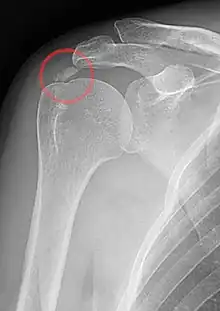

| A plain X ray of the shoulder showing calcific tendinitis | |

Calcific tendinitis is a common condition where deposits of calcium phosphate form in a tendon, sometimes causing pain at the affected site. Deposits can occur in several places in the body, but are by far most common in the rotator cuff of the shoulder. Around 80% of those with deposits experience symptoms, typically chronic pain during certain shoulder movements, or sharp acute pain that worsens at night. Calcific tendinitis is typically diagnosed by physical exam and X-ray imaging. The disease often resolves completely on its own, but is typically treated with non-steroidal anti-inflammatory drugs to relieve pain, rest and physical therapy to promote healing, and in some cases various procedures to breakdown and/or remove the calcium deposits.

Calcific tendinitis is typically diagnosed by physical examination and X-ray imaging.[1] During the formative phase, X-ray images typically reveal calcium deposits with uniform density and a clear margin.[1] In the more painful resorptive phase, deposits instead appear cloudy and with unclear margins.[1] By arthroscopy, formative stage deposits appear crystalline and chalk-like, while resorptive stage deposits appear smooth resembling toothpaste.[1] Ultrasound is also used to locate and assess calcium deposits. In the formative stage, deposits are hyperechoic and arc-shaped; in the resorptive stage deposits are less echogenic and appear fragmented.[1][3]